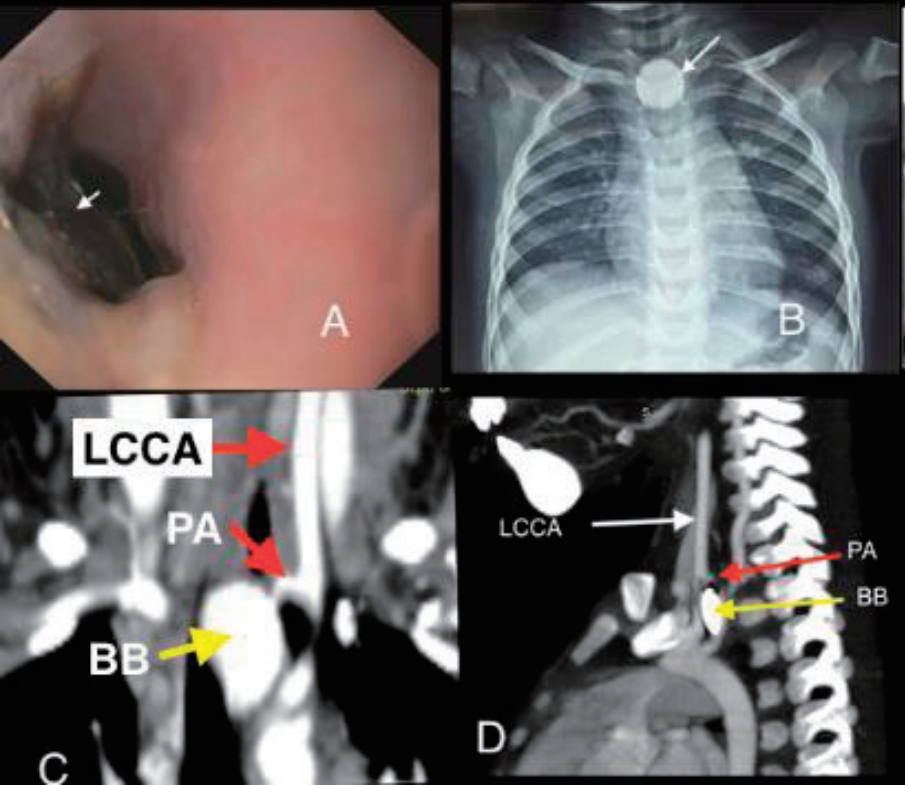

A previously well 18-month-old boy presented with 16 days history of poor feeding, fever and 2 episodes of clinically significant, well compensated upper gastrointestinal bleeding (UGIB) in the form of hematemesis and melena on day 10 and day 14 of illness respectively. He was transfused 2 units of packed red blood cells (PRBCs) elsewhere before presenting to us. On examination, the child was irritable, severely pale and had no splenomegaly. There was no history of witnessed foreign body ingestion. An urgent upper gastrointestinal endoscopy was performed after hemodynamic resuscitation which revealed an impacted foreign body in the upper esophagus with surrounding ulcerated mucosa (Fig. 1A). X-ray showed envisioned halo sign suggestive of BB (Fig. 1B). Computed tomography angiography (CTA) showed proximal left common carotid artery (CCA) pseudoaneurysm (4.9 mm×4 mm) in close proximity to BB suggestive of vascular fistula (Fig. 1C and D). Surgical consult was sought and BB removal was planned in operation theatre (OT) with cardiovascular and thoracic surgery back-up. Meanwhile, the child had another bout of massive UGIB requiring PRBC transfusions. After stabilization, the child was taken to OT and exploration was done via median sternotomy incision. Intraoperative findings included impacted BB in cervical esophagus and inflamed esophagus densely adhered to pretracheal fascia, left carotid sheath and prevertebral fascia. Intraoperative bleeding was seen at level of CCA, vascular control was ensured by using running sutures. BB was retrieved by intraoperative endoscopy by using grasping forceps. It was a lithium BB (20 mm×20 mm) (Fig. 2A). Esophagectomy with cervical esophagostomy, decompressive gastrostomy and feeding jejunostomy were done. Following surgery, feeding was established via jejunostomy. However, the child had right hemiparesis. CTA-head showed infarct in left parieto-temporal region involving middle and anterior cerebral artery territory (Fig. 2B and C). It was attributed to intraoperative compromised cerebral circulation due to probable clamping of branch of CCA while ensuring vascular control. Postoperative, child had fever, so antibiotics were upgraded from first-line (cefotaxime, amikacin and metronidazole) to piperacillin-tazobactum and teicoplanin. Blood culture grew Enterococcus fecalis sensitive to teicoplanin and child responded. Fortunately, hemiparesis has improved over the next one month and the child is on full enteral feeds and has a plan to restore anatomy after 3 months.

Fig. 1.

(A) Upper gastrointestinal endoscopy image showing an impacted foreign body (white arrow) in the esophagus with surrounding charred mucosa. (B) Halo sign on x-ray (anteroposterior view). (C) Computed tomography angiography (CTA; coronal section) showing the left common carotid artery (LCCA), a pseudoaneurysm (PA) (red arrow), and a button battery (BB) (yellow arrow). (D) CTA (sagittal section) showing the LCCA (white arrow), PA (red arrow), and BB (yellow arrow).